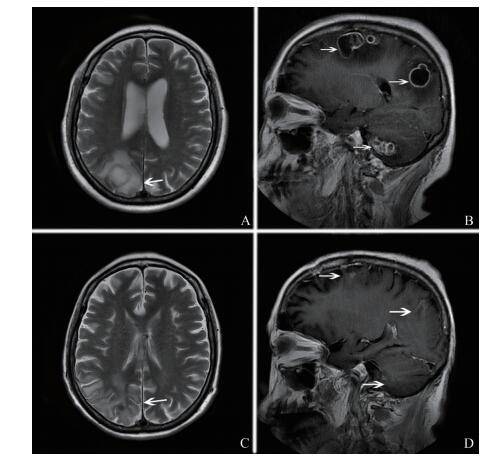

病例资料例1 患者女,26岁。因“咽痛4 d,发热伴意识模糊2 d”于2017年12月14日入中山大学附属第三医院。入院前4 d患者出现咽痛,呈持续性,伴轻微咳嗽,无明显咳痰,入院前2 d于坐车后出现呕吐1次,以胃内容物为主,休息后出现全身乏力、站立不稳,其后曾出现神志不清,随地大小便,体温最高达39.7 ℃。有SLE病史4年。发病前用药方案:硫酸羟氯喹0.2 g/次、2次/日,甲泼尼龙1 mg/次、1次/日。入院时体格检查:体温37.3℃,神志清晰,对答切题。双侧瞳孔等圆等大,直径3 mm,对光反射灵敏,双侧眼球外展受限,双侧眼底未见视乳头水肿。四肢肌张力正常,四肢肌力4级。颈软,颌胸距4 cm,克匿征阴性,巴宾斯基征阴性。心、肺、腹未见异常。实验室及辅助检查:血白细胞14.8×109/L,中性粒细胞0.87。腰椎穿刺示脑脊液压力320 mm H2O(1 mm H2O=0.0098 kPa),白细胞3.508×109/L,糖1.77 mmol/L,氯107.7 mmol/L,蛋白1.72 g/L。脑脊液涂片未发现病原体,脑脊液培养阴性。结核、真菌及病毒相关检查阴性。头颅MRI示脑膜脑炎,双侧额顶叶、放射冠、右侧侧脑室、右侧基底节及右侧海马旁回多发性病灶(图 1A、B)。脑脊液mNGS示鼻疽奴卡菌、特异序列数838、置信度高。诊断为诺卡菌脑膜脑炎,予磺胺甲

图 1 CNS诺卡菌感染例1患者头颅MRI A、B:治疗前头颅MRI增强图像显示右侧基底节片状异常信号影呈环状明显强化,并突向第三脑室内(A中箭头及B中箭头2所指处),有明显脑膜强化(B中箭头1所指处); C、D:治疗后头颅MRI增强图像显示右侧基底节片状异常信号影消失(C中箭头及D中箭头2所指处),未见明显脑膜强化(D中箭头1所指处) |

诺卡菌感染与其它脑脓肿一样,MRI下注射钆后显示出病变的坏死中心和多叶厚壁环状强化,T2加权像上的周边环形低信号被认为是由坏死组织碎片和巨噬细胞对夹膜的吞噬作用所形成,而厚荚膜的产生是因为诺卡菌生长缓慢及宿主抵抗细菌的过程中所发生的外周变化[9-10]。诺卡菌感染若能早期治疗,病灶可明显减少、缩小。